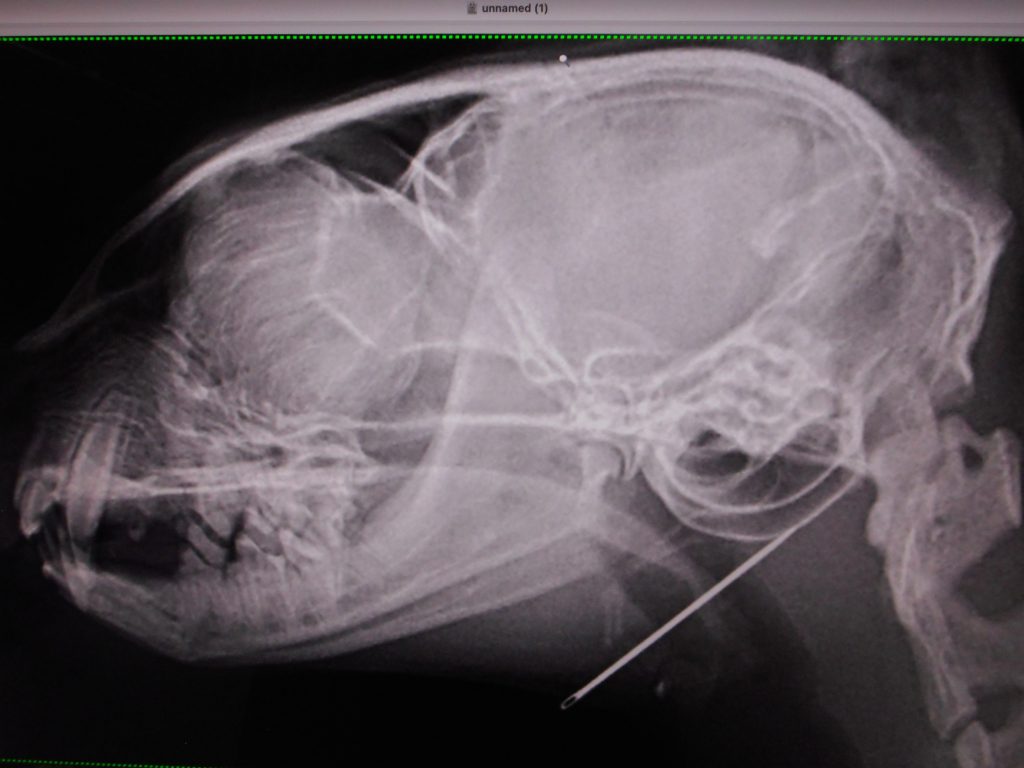

まずは、レントゲン検査

💦

下手に動くとやばいところに刺さりそう

他にもないか全身のレントゲン検査

結果、この1本勝負

さぁ、どうやって摘出するか?